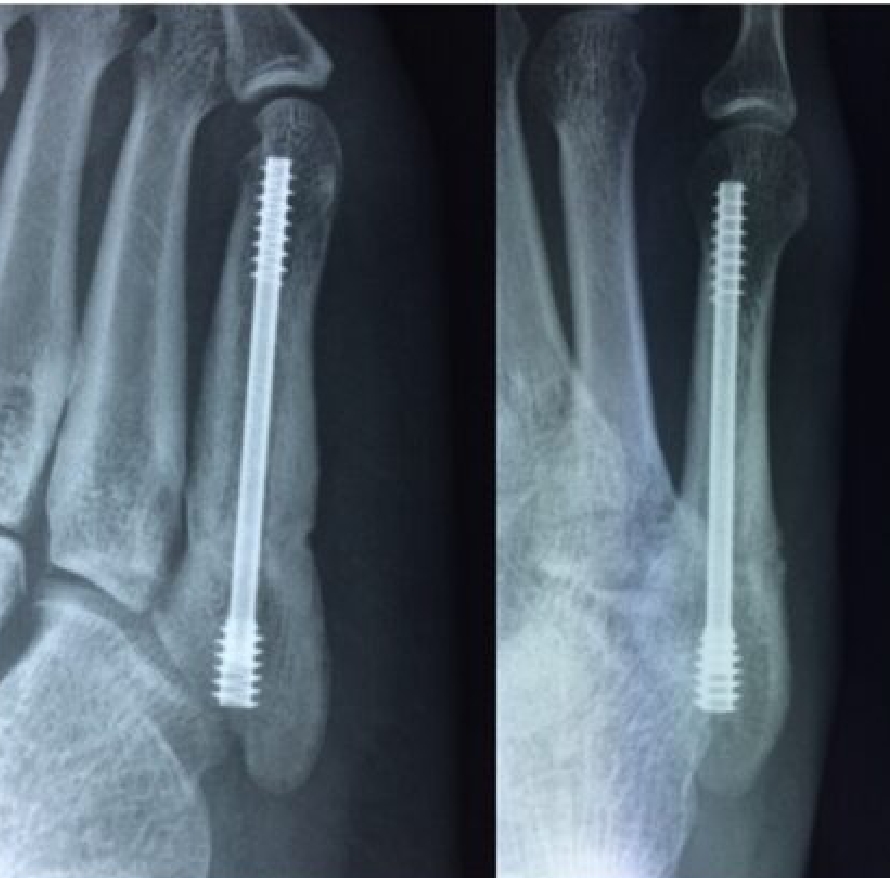

2020-12-09 スポーツ整形 ページ内リンク 第5中足骨骨折(ジョーンズ骨折)【スポーツ整形外科】 第5中足骨骨折(ジョーンズ骨折)【スポーツ整形外科】 サッカーやバスケット等の切り返しの多い競技にしばしば発生する。⇒スクリューによる固定で2〜3か月で復帰。 術前 術後 術後12週間 杉本 武 副院長/スポーツ整形外科センター長 整形外科スポーツ整形 詳しく見る 板野 佑生 整形外科スポーツ整形 詳しく見る 関連ページ スポーツ整形 一覧へ戻る